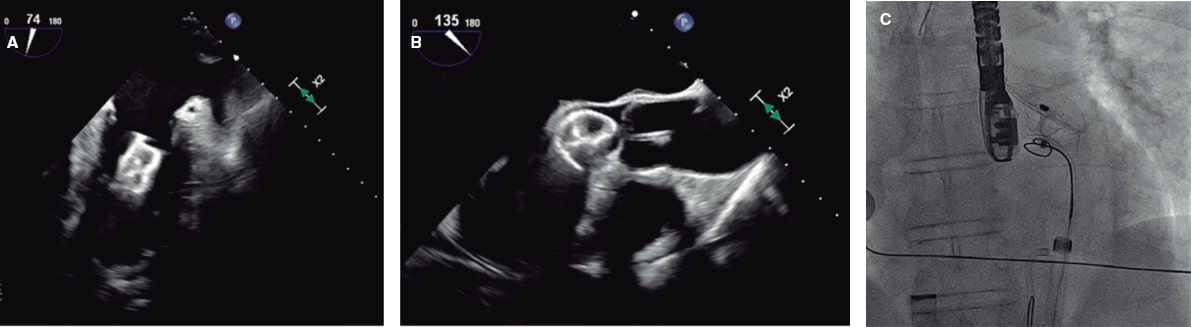

En la figura 5 y la figura 6 se muestran algunos ejemplos de embolización de dispositivos de cierre de la orejuela izquierda.

Figura 5. Ecocardiograma transesofágico (ETE) intraprocedimiento y fluoroscopia de cierre de la orejuela izquierda con un dispositivo Amulet de 25 mm. A: el dispositivo migró al ventrículo izquierdo (VI). B: se introdujo por un acceso femoral izquierdo un catéter guía JR4 de 8 Fr con un lazo de 20 mm que agarró el dispositivo por el tornillo del lóbulo distal y permitió traccionarlo a la aorta descendente. C: a continuación se canalizó la arteria femoral derecha con un introductor de 16 Fr, y con un catéter guía y un lazo de 30 mm se volvió a agarrar el dispositivo por el tornillo del lóbulo distal, que fue traccionado y finalmente extraído.